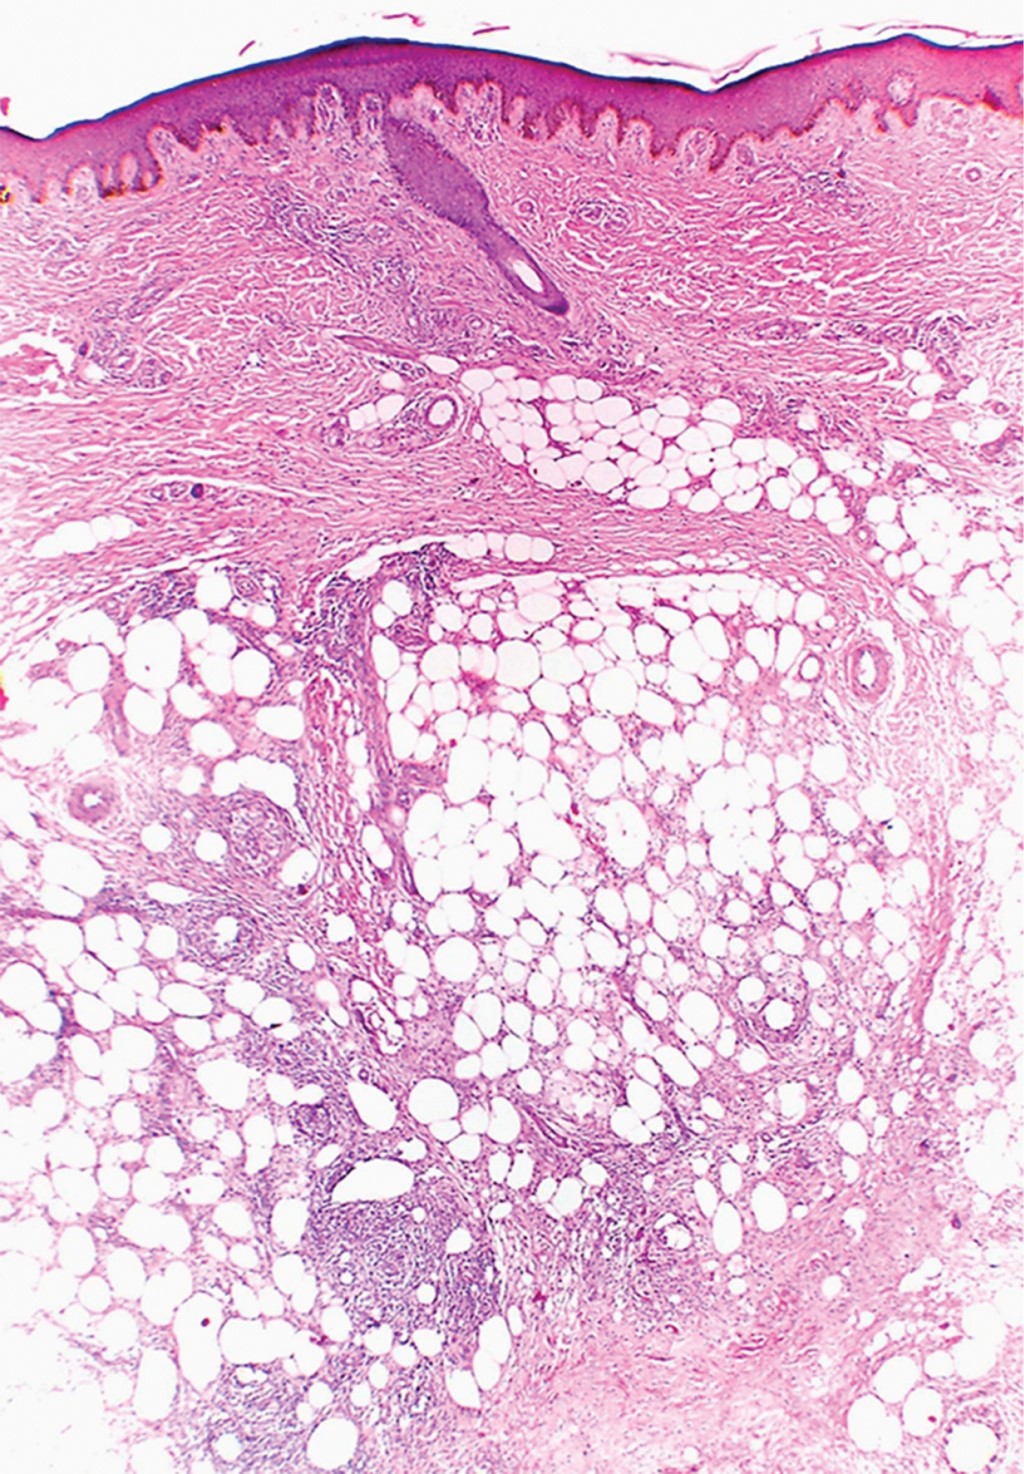

Se realizó nueva biopsia de uno de los nódulos. La imagen histopatológica mostró moderados infiltrados linfohistiocitarios perivasculares y perianexiales en dermis superficial y media. En dermis profunda y tejido celular subcutáneo, tanto en la porción septal como en la lobulillar, se apreciaban moderados infiltrados en focos constituidos por linfocitos, histiocitos, células epitelioides, esbozos de células gigantes multinucleadas, células gigantes tipo Langhans y de tipo cuerpo extraño. Dicho infiltrado invadía algunos vasos (Figura 2). Con lo anterior se realizó el diagnóstico histopatológico de paniculitis mixta granulomatosa con daño vascular.

Figura 2